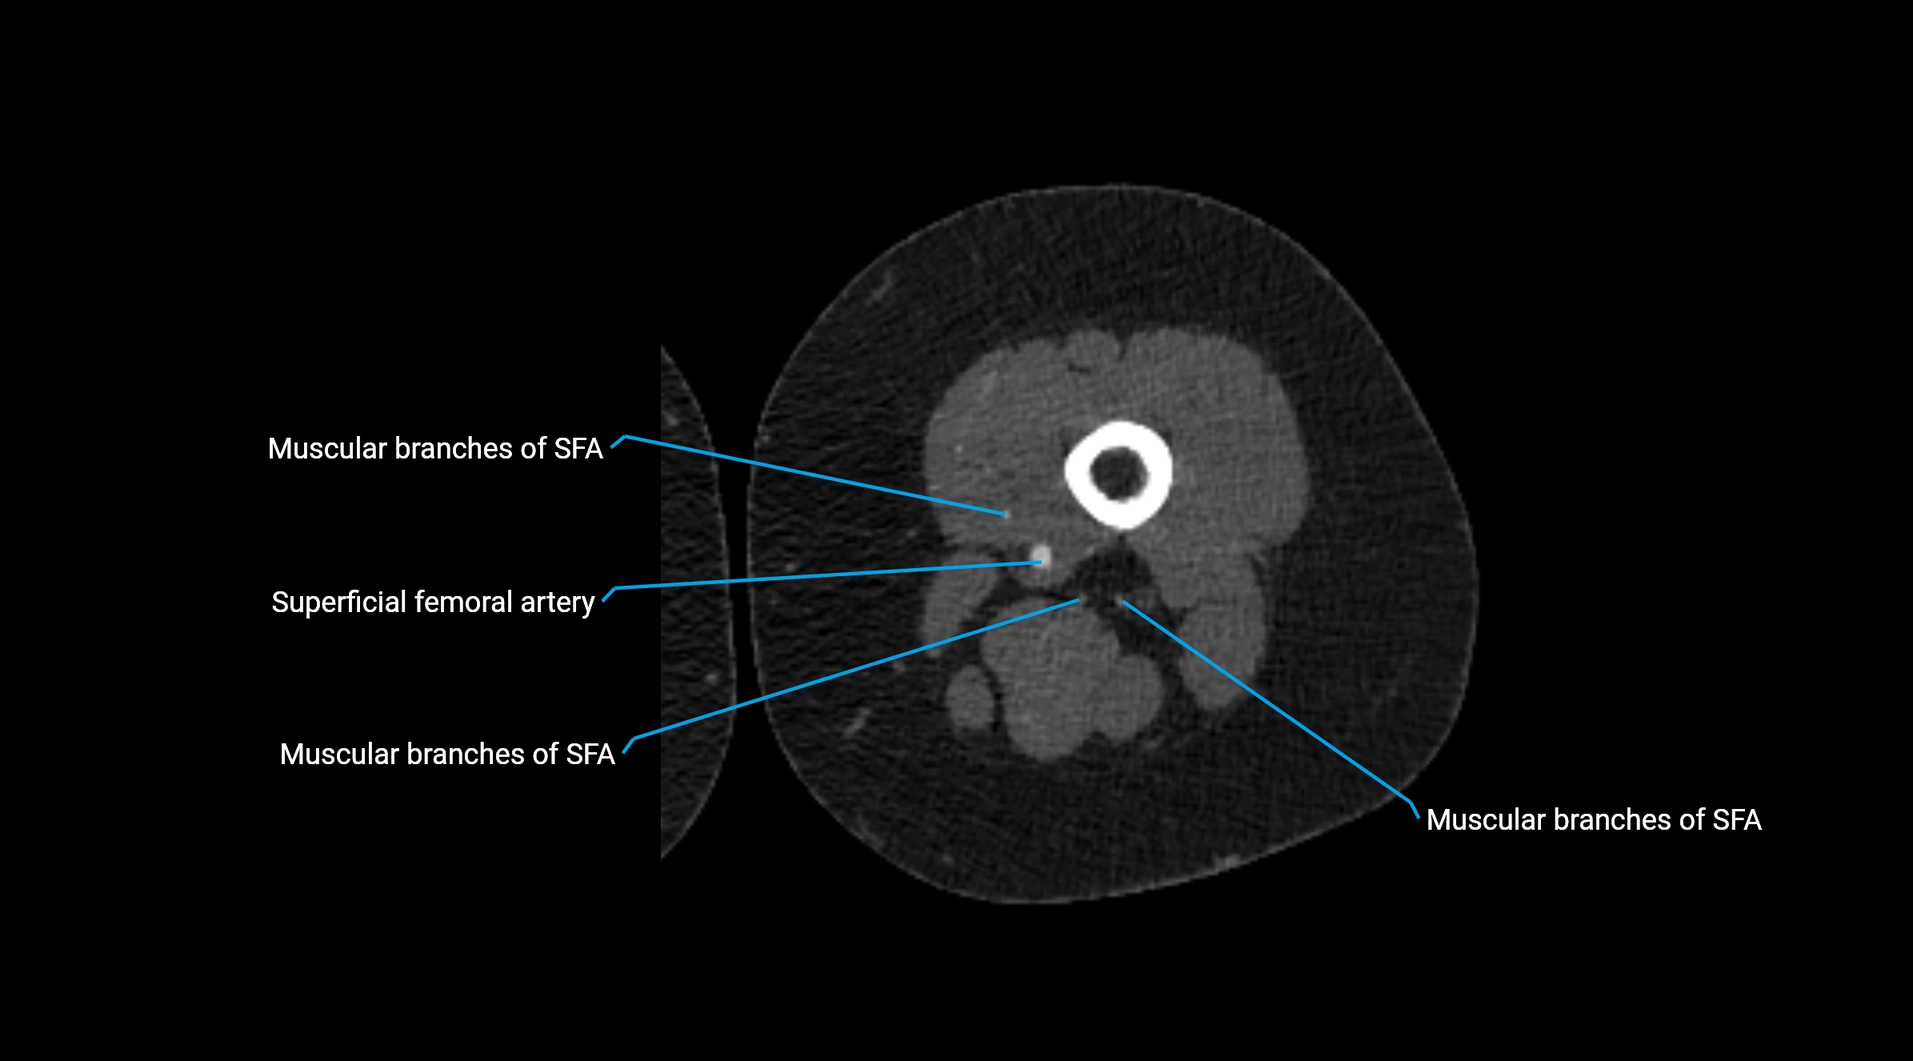

Contrast-enhanced CT (CTA):

• Gold standard for abdominal aortic imaging

• Provides excellent detail of lumen, wall, aneurysm, thrombus, and branch vessels

• Multiplanar and 3D reconstructions help in aneurysm measurement, stent graft planning, and dissection evaluation